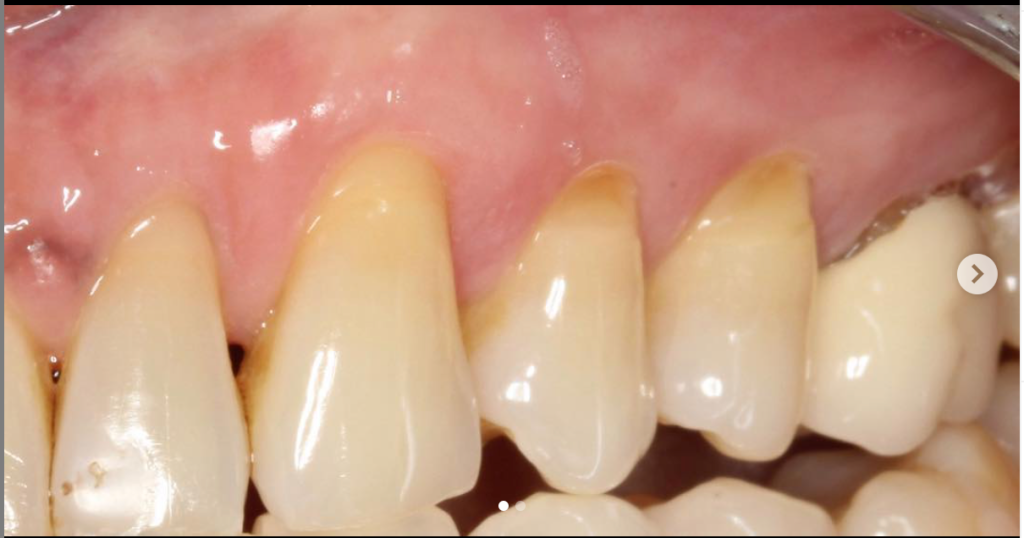

Connective Tissue Gingival Grafting for Gingival Recession